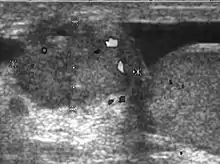

Teratoma Although teratoma is the second most common testicular tumor in children, it affects all age groups. Mature teratoma in children is often benign, but teratoma in adults, regardless of age, should be considered malignant. Teratomas are composed of all three germ cell layers, i.e. endoderm, mesoderm and ectoderm. At ultrasound, teratomas generally form well-circumscribed complex masses. Echogenic foci representing calcification, cartilage, immature bone and fibrosis are commonly seen [Fig. 5]. Cysts are also a common feature and depending on the contents of the cysts i.e. serous, mucoid or keratinous fluid, it may present as anechoic or complex structure [Fig. 6].

![Fig. 5. Teratoma. A plaque-like calcification with acoustic shadow is seen in the testis.[citation needed]](../I/Ultrasonography_of_teratoma.jpg.webp) Fig. 5. Teratoma. A plaque-like calcification with acoustic shadow is seen in the testis.

Fig. 5. Teratoma. A plaque-like calcification with acoustic shadow is seen in the testis.![Fig. 6. Mature cystic teratoma. (a) Composite Image. Mature cystic teratoma in a 29-year-old man. Longitudinal sonography image of the right testis shows a multilocular cystic mass. (b) Mature cystic teratoma in a 6-year-old boy. Longitudinal sonography of the right testis shows a cystic mass containing calcification with no obvious acoustic shadow.[citation needed]](../I/Ultrasonographies_of_mature_cystic_teratomas.jpg.webp) Fig. 6. Mature cystic teratoma. (a) Composite Image. Mature cystic teratoma in a 29-year-old man. Longitudinal sonography image of the right testis shows a multilocular cystic mass. (b) Mature cystic teratoma in a 6-year-old boy. Longitudinal sonography of the right testis shows a cystic mass containing calcification with no obvious acoustic shadow.